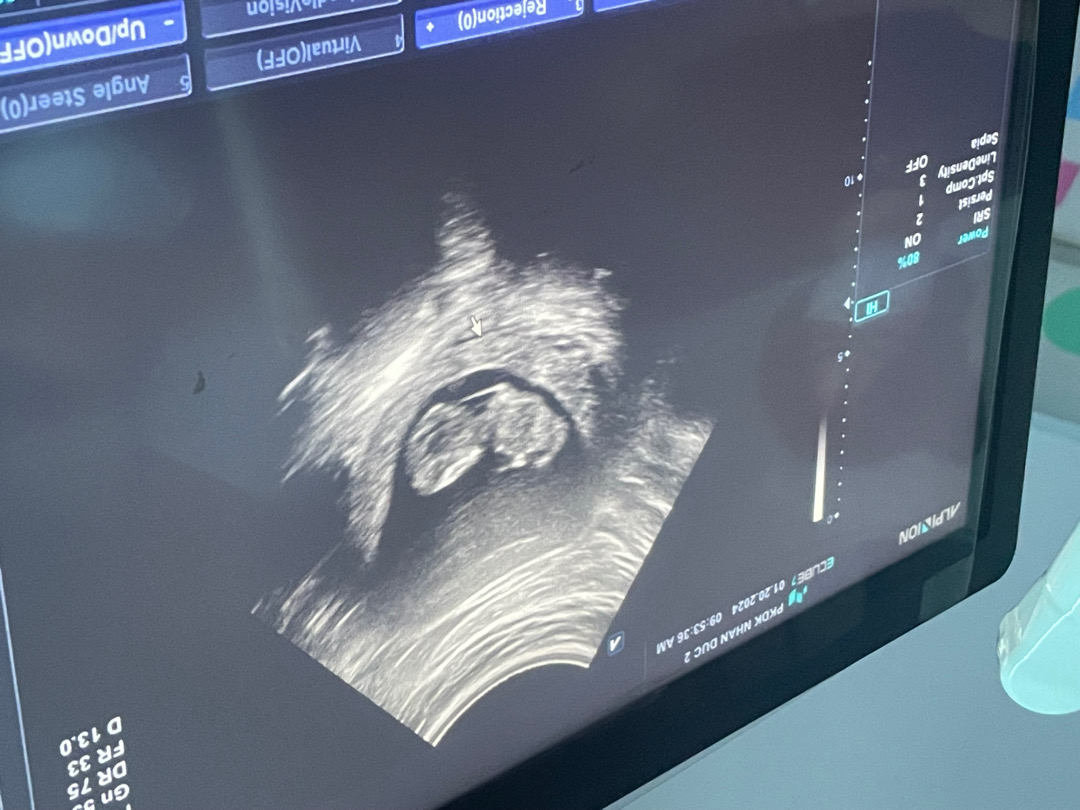

성별테스트기해보세용! 10주부터알수있대요

성별 알 수 있을까요?

아들, 딸 다 상관이 없긴하지만 너무 궁금해요 각도법?으로 알 수 있을까요?ㅠㅠㅠ

12주~15주 사이 각도법으로 보시면 얼추? 알수있어요